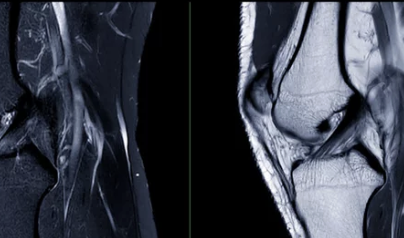

1. 무릎에 물이 찬다는 건 어떤 상태일까

무릎 관절에는 원래 소량의 관절액이 존재합니다.

이 관절액은 관절을 부드럽게 움직이게 하고 충격을 완화하는 역할을 합니다.

하지만

염증, 손상, 퇴행 변화가 생기면

관절액이 과도하게 분비되면서 무릎이 붓고 압박감이 생깁니다.